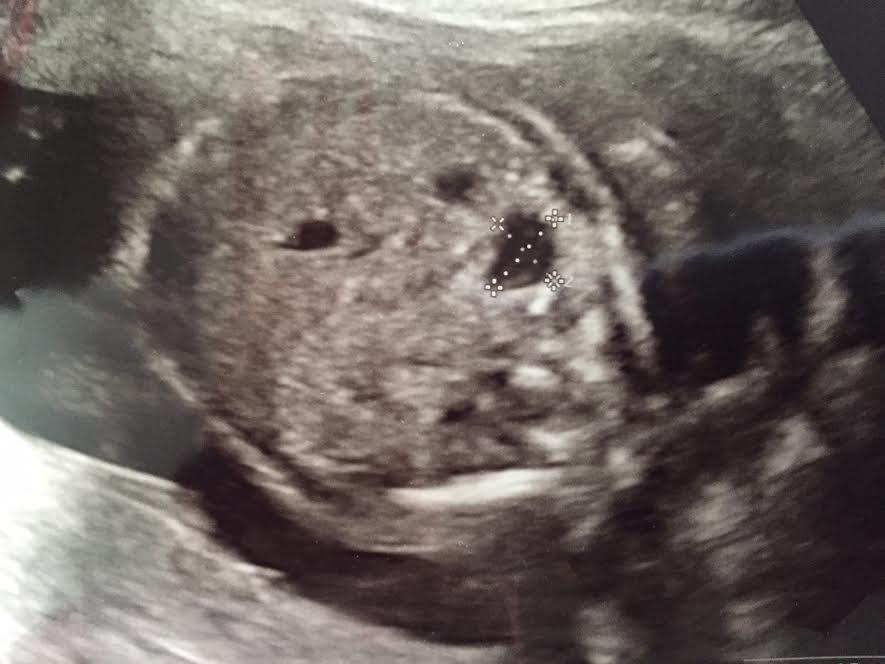

vastaanotolta tusinoittain möykkykuvia mukanani. (Kuvassa kaksi ylhäällä olevaa mustraa reikää ovat munuaiset. Oikean munuaisen alapuolella on epämääräinen musta möykky.)